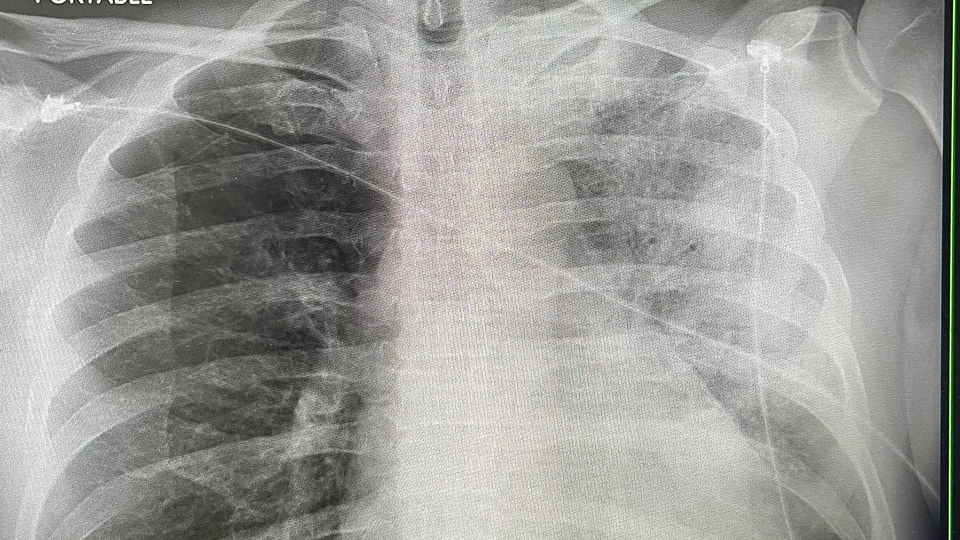

Tanı konma süreci hakkında bilgi veren Dr. Öğr. Üyesi Alış, “Fizik muayene, kanda enfeksiyonu gösteren tetkikler, akciğer grafisi, gerekirse akciğer bilgisayarlı tomografisi ile tanı konulabilir. Etkenin kendisine yönelik idrarda bakılan bir test, balgam kültürü yapılabilir. Tedavide geç kalınırsa hastalık ağır ve yüzde 10 oranında ölümcül seyredebilir” açıklamasında bulundu.